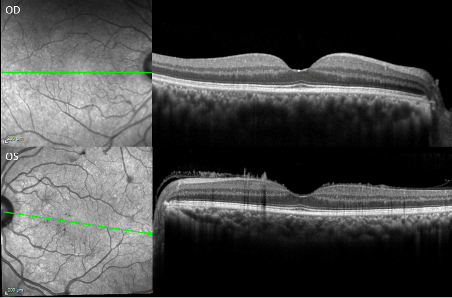

Slit lamp photography of both eyes showing the posterior lenticular deposits with glass wool-like vitreous opacities in the anterior vitreous.

Optical coherence tomography of macula of both eyes. The left eye reveals needle-shaped deposits on the anterior retinal surface extending into the vitreous.